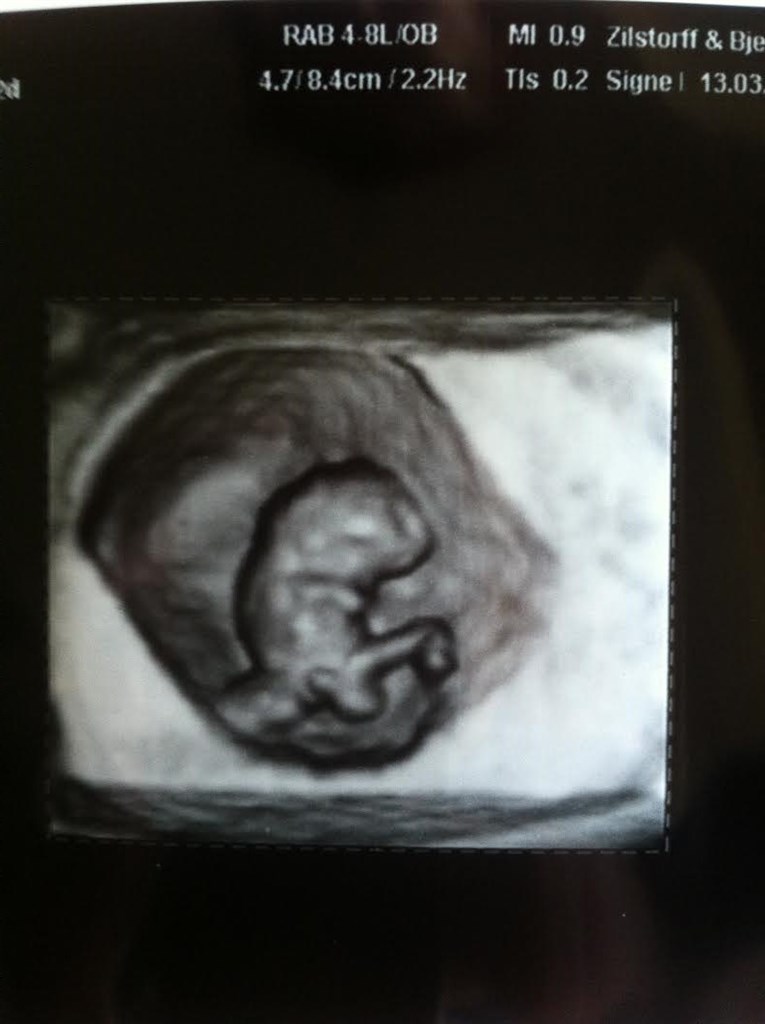

Så ramte jeg uge 9+2

Den har det godt den lille og vokser derud af. Den lå og sprallede rundt derinde

Terminen er sat til den 13 okt